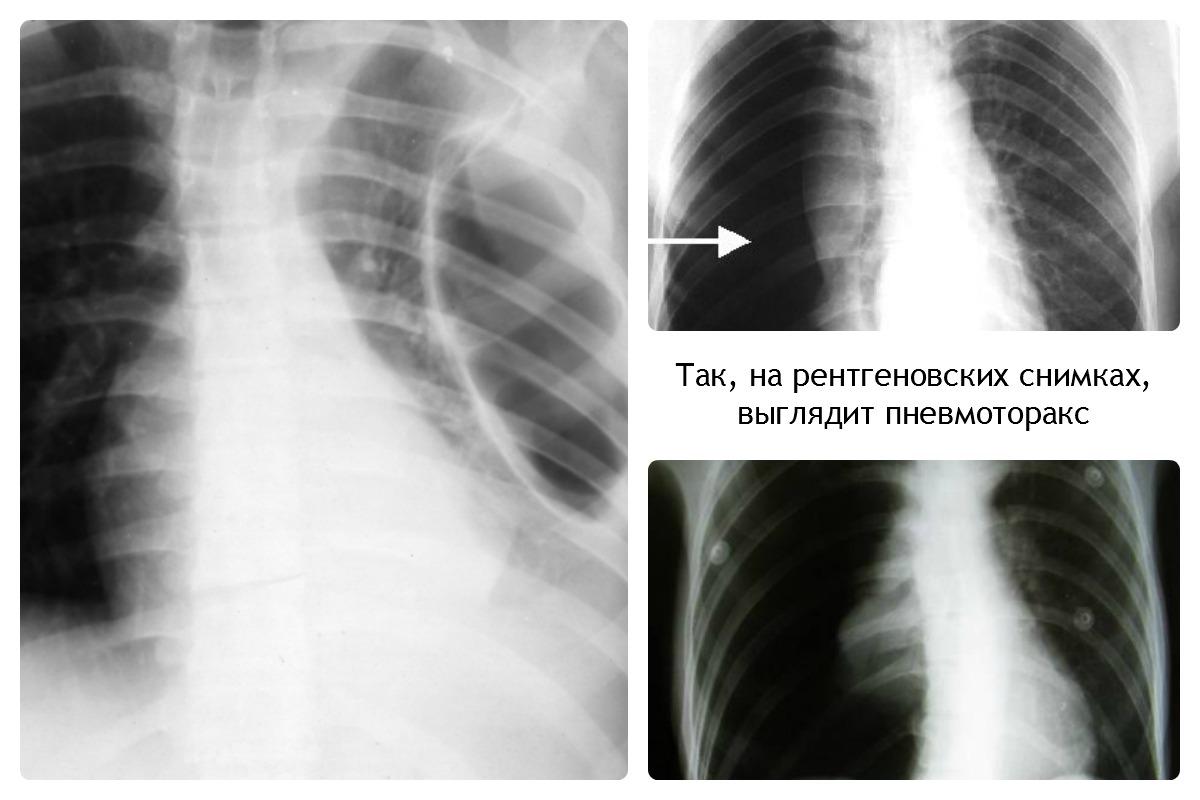

Определить наличие воздуха в плевральной полости самостоятельно невозможно. Начало этого процесса можно заподозрить только по клиническим проявлениям заболевания. Обратите внимание на изображение пневмоторакса:

Диагностика пневмоторакса осуществляется с помощью рентгенографии. На рентгеновском снимке он будет представлен как светлый участок, не имеющий легочного рисунка. Это состояние возникает в результате накопления воздуха в плевральной полости.

При длительном течении заболевания наблюдается спадание легочной ткани, что отчетливо видно на рентгеновском снимке.

Для подтверждения диагноза пневмоторакса используются различные методы визуализации. Наиболее распространенным является рентгенография грудной клетки, которая позволяет выявить наличие воздуха в плевральной полости. На рентгеновских снимках пневмоторакс проявляется в виде темного пространства между легким и грудной стенкой, где отсутствует легочная ткань.